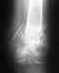

Похоже, есть смысл не ждать, а переделать.